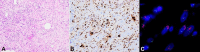

Retroperitoneal liposarcomas are rare tumors arising from the soft tissue of the retroperitoneum and are of mesenchymal cell origin. They can reach a large size prior to causing symptoms and generally have a poor prognosis. We present the case of a 93-year-old lady presenting with a large retroperitoneal liposarcoma at the site of a previous colonic anastomosis for the adenocarcinoma treatment. It caused minimal symptoms initially, but surgical resection was undertaken when the tumor was found to be growing significantly in size. However, due to the tumor's location and its invasion into surrounding structures, the resection was not feasible and subsequently abandoned. A retroperitoneal liposarcoma arising from the site of a previous colonic resection has not been previously described. A review of the diagnosis and current management of these lesions is also given.